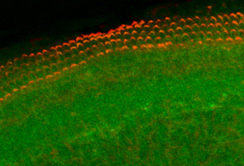

Mit Hilfe von Nanopartikeln könnten in Zukunft Hörschäden therapiert werden. (grün=Nanopartikel, rot=Sinneshärchen)